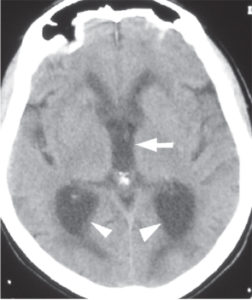

• Figure 2.10. CT of patient w/ normal pressure hydrocephalus. Note the dilated atria of the lateral ventricles (arrowheads) and rounded third ventricle (arrow) on this image. This is from a patient with normal pressure hydrocephalus. Neurosurgery, Brunicardi F, Andersen DK, Billiar TR, Dunn DL, Hunter JG, Matthews JB, Pollock RE. Schwartz’s Principles of Surgery, 10e; 2014. Accessed: July 27, 2018.

Abnormalities in the production, absorption, or flow of CSF result in ventricular dilatation, with no increases in overall intraventricular pressure. This is oftentimes an idiopathic disorder that is most common after 60 years of age.

• A group of clinical findings that is characteristic of NPH includes: a slowly progressive gait disorder that is usually the earliest feature, followed by impaired of mental function and, later, urinary incontinence.